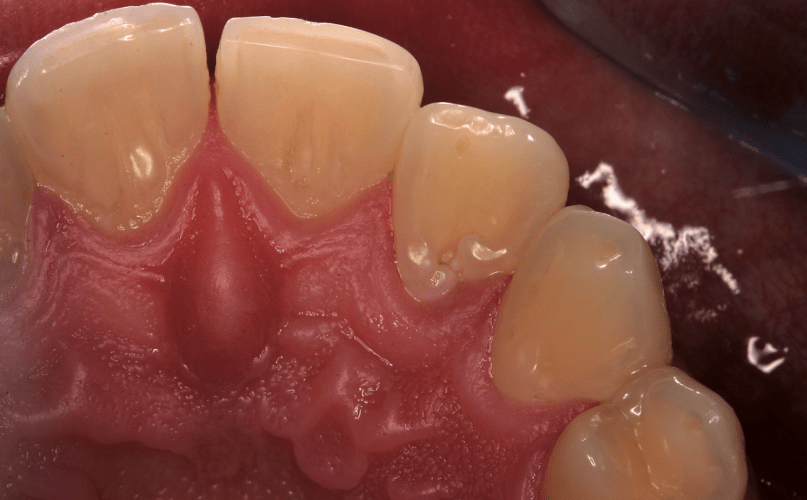

Der Patient berichtete von einer Fistelbildung vor ca. zwei Jahren im Bereich des Zahnes 12. Die Behandlung erfolgte ausschließlich durch eine Antibiotikagabe, wodurch eine Heilung der Fistel eintrat. Vor einigen Wochen bildete sich nun erneut eine Fistel. Trotz Antibiotikagabe entwickelte sich ein Abszess im Bereich 12, den der Patient selbstständig eröffnete. Bei der Vorstellung im UMG hatte der Patient keine Schmerzen. Auf Palpation der Umschlagfalte hin war der Bereich 11/21 leicht druckdolent. Zusätzlich lag eine erbsengroße, leicht fluktuierende Schwellung vor. Ein Fistelmaul war nicht zu erkennen, es lag eine Rötung der Region vor. Der Patient wurde zur Weiterbehandlung in die Abteilung Präventive Zahnmedizin, Parodontologie und Kariologie überwiesen. Die klinische Befunderhebung zeigte eine Einziehung der klinischen Krone des Zahnes 12 (Abb. 2). Die Sondierungstiefen waren physiologisch und lagen zwischen 1 und 2mm. Der Sensibilitätstest an den Zähnen 11 und 13 fiel positiv, an Zahn 12 negativ aus. Ein erhöhter Lockerungsgrad lag nicht vor. Der Zahn wies klinisch und röntgenologisch keine Karies auf.

Im vorliegenden Fall kam es aufgrund der Invagination und damit einer Verbindung zwischen Mundhöhle und Pulpa des Zahnes 12 zu einer Pulpanekrose und Abszessbildung. Schon an der Form der klinischen Krone konnte die Einziehung palatinal erkannt werden. Das Röntgenbild zeigte ebenfalls eine Aufhellung mit schmelzähnlicher Transluzenz im Kronenbereich und koronalen Wurzeldrittel, was auf eine Invagination hindeutet (Abb. 2). Zusätzlich führten der negative Sensibilitätstest, die Abszessbildung und die ausgedehnte Parodontitis apicalis zur Diagnose Dens invaginatus mit Pulpanekrose und ausgedehnter Parodontitis apicalis und Abszessbildung. Die Therapie dieses Zahnes bestand aus einer Wurzel­kanalbehandlung. Es wurde zusätzlich aufgrund des häufigen bilateralen Befalls die kontralaterale Seite auf eine Invagination untersucht, um einer Pulpanekrose vorzubeugen. Die Einziehung am Zahn 22 war bei dem Patienten bereits zu einem früheren Zeitpunkt versiegelt worden. Die Schwierigkeit bei der endodontischen Behandlung eines Dens invaginatus bildet die vollständige Erschließung, Desinfektion und Obturation der sehr variablen und komplexen anatomischen Formen der Invagination. Trotz Einteilung der Invagination in verschiedene Typen nach Oehlers5 können zahlreiche Variationen vorliegen.